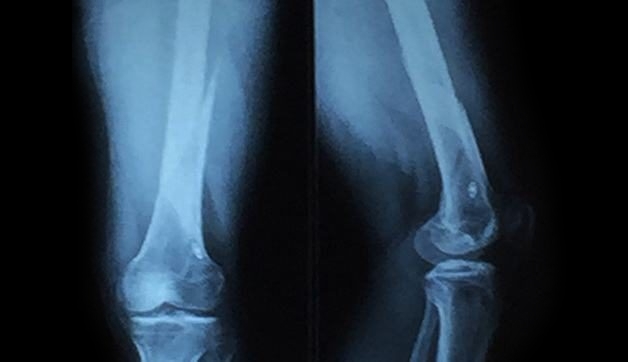

Chụp X quang cho vùng chân là kỹ thuật chẩn đoán hình ảnh sử dụng một lượng nhỏ tia bức xạ (tia X) để ghi lại hình ảnh cấu trúc vùng chân, bao gồm cả mô mềm và xương chân trên phim chụp.

Hình ảnh chụp X quang có thể hiển thị xương ghe, cổ chân, xương ngón chân,… Thông thường, bác sĩ chẩn đoán hình ảnh sẽ chỉ định chụp X quang cho vùng chân ở vị trí chân bệnh nhân cảm thấy đau hoặc có tổn thương. Tuy nhiên, một số trường hợp sẽ cần chụp X quang ở cả hai chân, kể cả chân không bị thương để có thể so sánh tình trạng.

Chụp X quang cho phép bác sĩ có thể quan sát các mô mềm, xương chân và có thể phát hiện những tổn thương bất thường trên phim chụp

– Bước 4: Tiến hành chụp X quang, thời gian chụp diễn ra rất nhanh chóng. Trong quá trình chụp, bác sĩ/ kỹ thuật viên có thể thay đổi vị trí chân nhiều lần để đảm bảo thu được hình ảnh ở nhiều góc độ khác nhau của chân. Thông thường, phim chụp sẽ hiển thị mặt trước và hai mặt hai bên của chân.